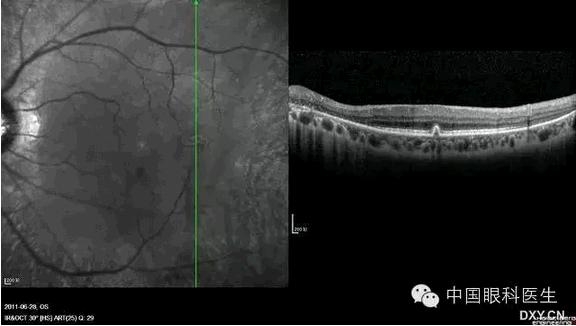

视网膜色素变性:除黄斑区仅余的IS/OS反射光带外,余未见IS/OS反射光带。